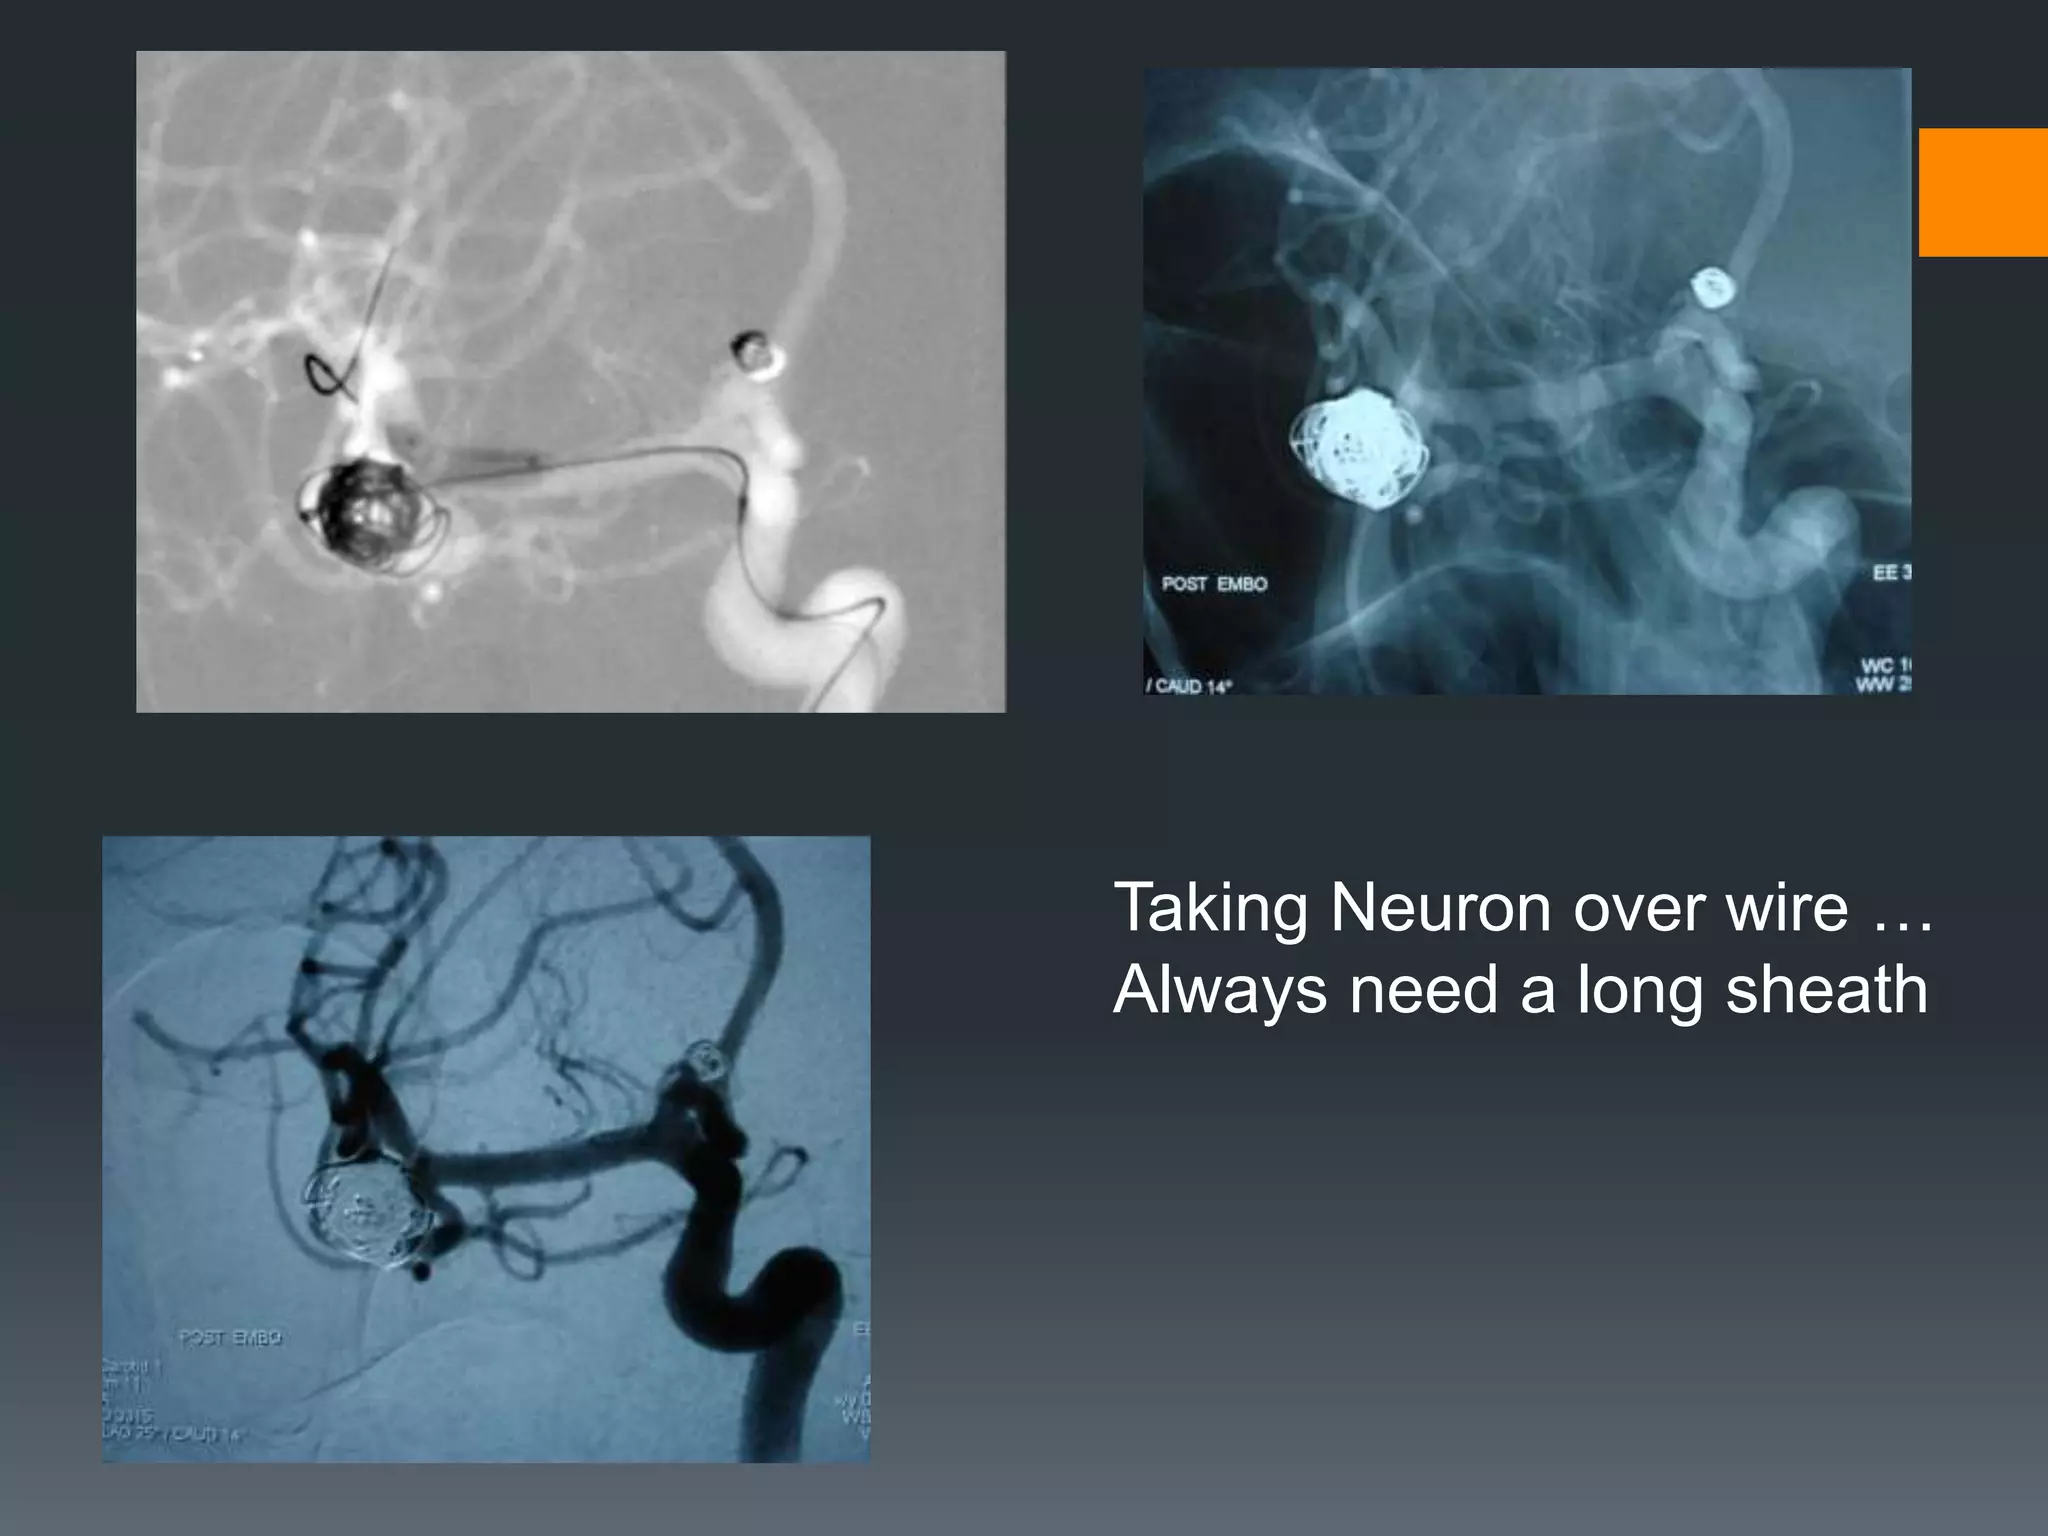

This document discusses tricks and techniques for difficult cannulations during neurointerventional procedures. It outlines strategies for accessing the aortic arch, internal carotid artery (ICA), and areas distal to aneurysms. Long sheaths, distal access catheters, and co-axial techniques are presented as options that have improved cannulation success. Guidance on sheath and catheter selection is provided for different vessel paths. The importance of catheter placement as high as possible in the ICA is emphasized. Reverse curve cannulations are also mentioned. Overall, the document stresses that careful cannulation is critical for procedural success and different strategies may be needed depending on the vessel target.